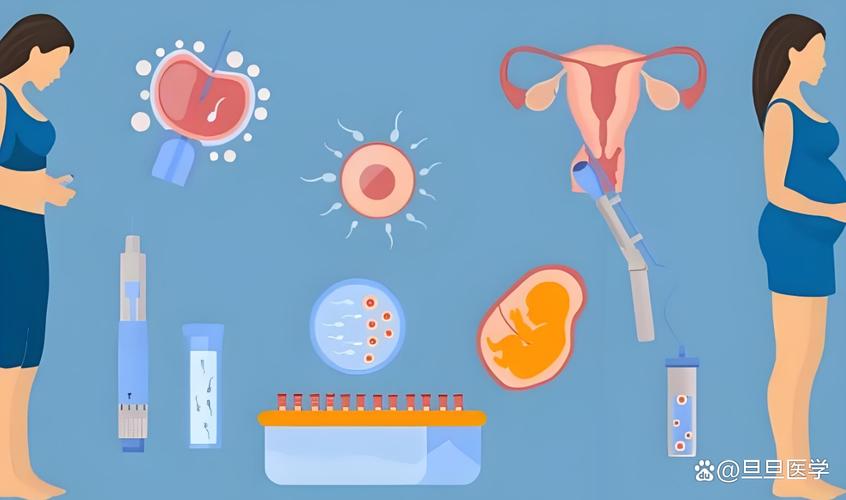

说起试管婴儿,很多人会想到“高科技”、“昂贵”等词,但很少有人会想到“失败”。然而,试管婴儿胚胎培养的失败是真实存在的,它给许多家庭带来了沉重的心理和经济负担。今天,我们就来谈谈试管婴儿胚胎培养失败的原因及其解决方案。

试管婴儿胚胎培养失败是一个复杂的问题,涉及到胚胎质量、母体因素、操作技术等多个方面。只有综合考虑这些因素,采取针对性的措施,才能提高试管婴儿的成功率,帮助更多的家庭实现生育梦想。